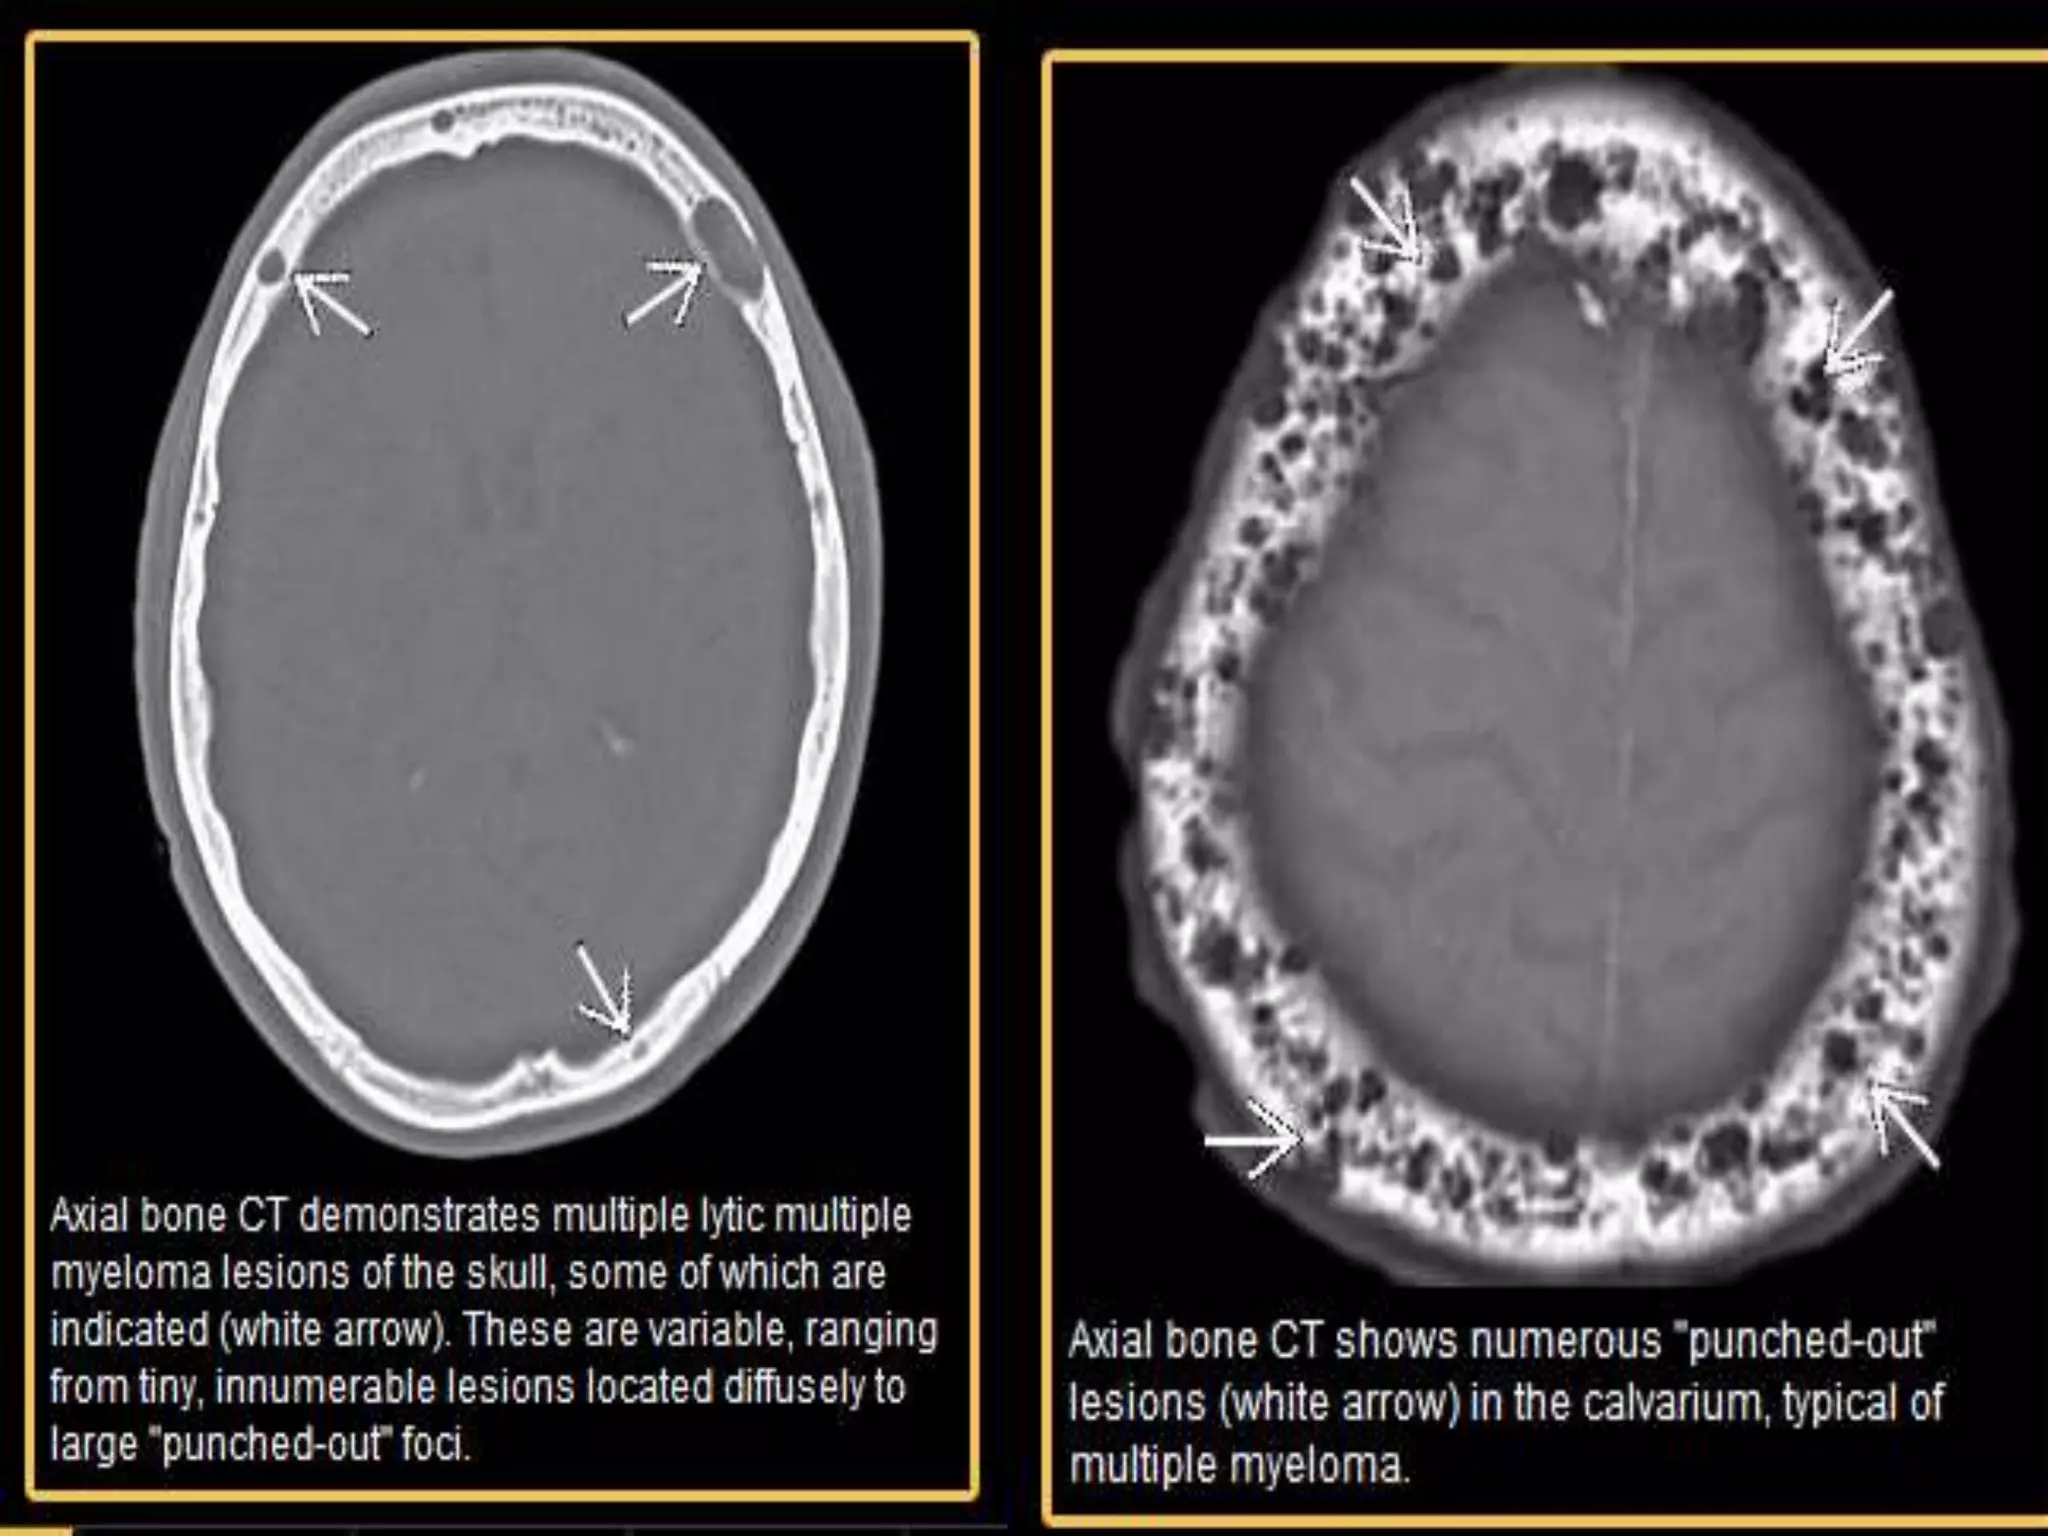

Multiple Myeloma

• A malignant bone marrow disorder characterized by

monoclonal proliferation of plasma cells.

• Responsible for most primary bone lesions in advanced

ages.

• The solitary form is designated by plasmacytoma.

• Typically appear as well-defined multiple, discrete, small,

punched out lytic lesions without marginal sclerosis

‘rain-drop’ lesions coalesce to form larger lesions lytic

lesions, resembling punch holes.

• “pepper pot skull”

NECT:

• Punched out lytic lesion;

cortex is eroded from within

sharply defined margins

Fig: Uncountable lytic "punched out" lesions on the lateral

skull radiograph, typical of multiple myeloma.

Fig: Myeloma lytic skull lesions on non-enhanced CT scan (a) of the same

patient . MRI accurately depicts myelomatous infiltration with replacement of

normal bone marrow as demonstrated in this T1-weighted images after

gadolinium administration, showing anomalous enhancement with multiple

lesions, which had a permeative pattern and T2 hyperintensity.